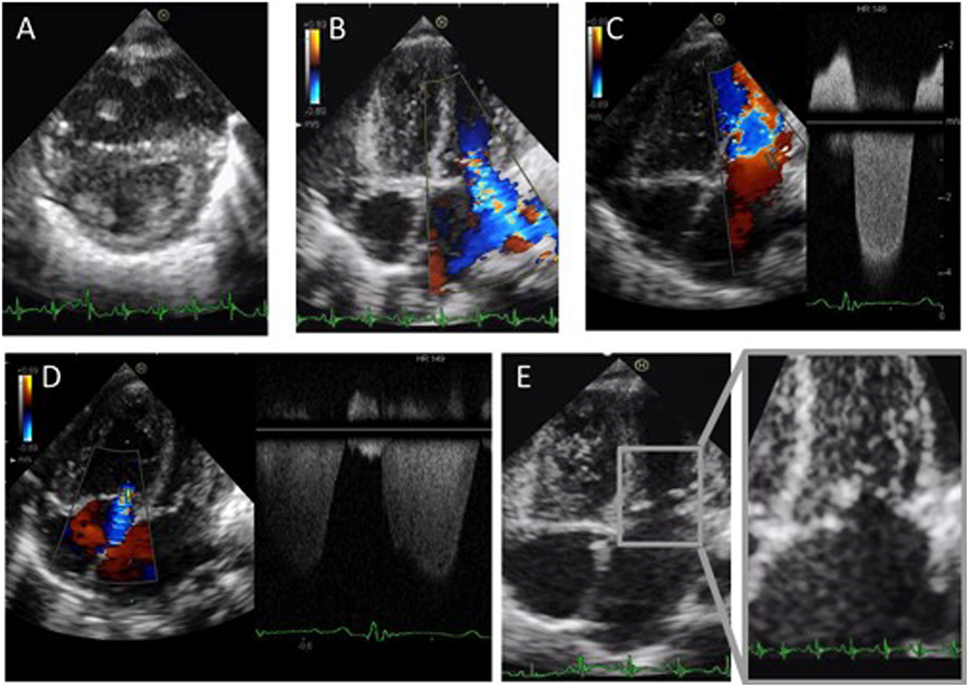

心臓波超音波検査を施行したところ,左室は右室に圧排され狭小化(左室拡張末期径=17.2 mm)しており,高い右室圧が示唆された.moderate-severe MRを認め,MSに関しては,左室流入血流はE peak velocity 2.26 m/secと加速し,mean PGは8.4 mmHgと高値であった.重症MSRを認め,三尖弁逆流圧格差(TRPG)は69 mmHgと高値で,oversystemic PHの状態であった(Fig. 2, Movie 1).

Pediatric Cardiology and Cardiac Surgery 34(4): 215-221 (2018)

Fig. 2 Echocardiographic evaluation on admission

A) Left ventricular (LV) short-axis view. B) Moderate to severe mitral regurgitation (MR). C) Transmitral E peak velocity is measured as 2.26 m/s. D) Tricuspid regurgitation pressure gradient (TRPG) is 69 mmHg. E) Mitral valve leaflet is thickened and chordae tendineae are shortened.

僧帽弁を観察したところ,僧帽弁尖は前尖,後尖ともに肥厚し,エコー輝度の上昇を認めた.また腱索が短く,そのためにtetheringが生じ,coaptationが不良であった(coaptation height: 2.7 mm, coaptation depth: 6.6 mm)(Table 2, Movie 2).動脈管は閉鎖しており,血行動態に影響はなかった.